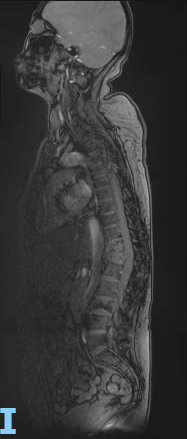

脊柱MR:T11-12、L3椎体发生压缩性骨折,考虑骨转移所致,T12椎体挤压椎管狭窄、变形。T8-L4多发转移。

治疗仅8周后,复查胸CT、腹盆CT、头MR、肿瘤标志物,评效结果为缩小的SD,肿瘤标志物下降,肝功能恢复正常。基线27mm的肺部病灶在持续治疗中不断缩小,至2025年4月CT复查完全消失,并维持至今。脑转移灶5mm缩小至2-3mm。